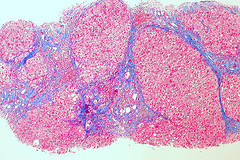

But when inflammation occurs with fatty liver, liver tissues can become scarred. This is called fibrosis. Should the fibrosis scarring worsen, cirrhosis may develop. During cirrhosis the liver begins to shut down — often termed liver failure.